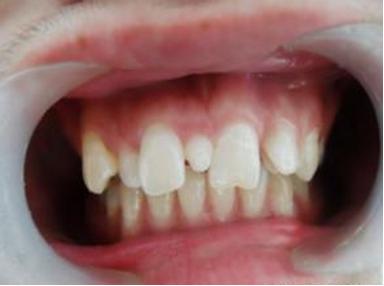

李奶奶的宝贝孙子六岁半了,上颌前面的两颗门牙已经替换了三个多月,可是两颗新牙间缝隙不见变小,反而越来越大了,远没有乳牙长得那么整齐,马上要上小学了,和其他孩子相比,门牙有大缝这事最近让李奶奶一直着急上火,平日总挂在脸上的笑容也不见了,今天一大早就带着孩子到口腔科检查。

多生牙常常导致正常恒牙发育和萌出障碍,表现为恒牙迟萌或阻生、牙根弯曲、牙齿移位或萌出方向改变,伴随的就是乳牙滞留、邻牙扭转、牙齿出现间隙等,有时还会造成邻牙牙根的异常吸收,形成滤泡或牙源性囊肿。有的多生牙虽不会表现为上述复杂的情况,但排在牙列中有碍美观才引起患儿和家长的关注。